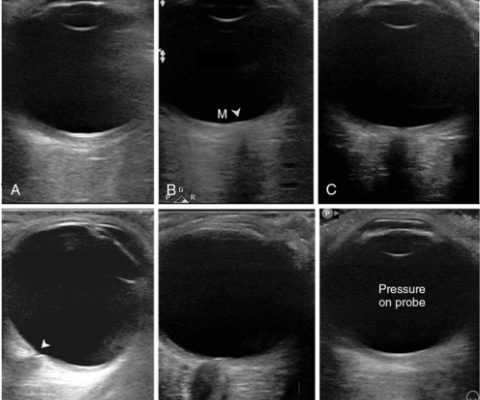

Göz ve orbita ultrasonu, yüksek frekansta ses dalgalarının kullanıldığı bir görüntüleme yöntemidir. Bu yöntemde, ultrason cihazı tarafından gönderilen ses dalgaları, gözün iç yapısına ve orbita (göz çevresi) bölgesine çarpar ve yankılanır. Bu yankılar, bilgisayar tarafından detaylı bir şekilde işlenerek görüntüler oluşturulur. Bu görüntüler, gözün içindeki yapıları, tümörleri, kistleri veya diğer anormallikleri gösterir.

Ultrason probu, jelli bölgeye yerleştirilir ve ses dalgaları gözün iç yapısına gönderilir. Bu dalgalar, çeşitli dokuların sınırlarını ve özelliklerini yansıtarak bilgisayar tarafından görüntüler oluşturur.

Elde edilen görüntüler, bir göz uzmanı veya radyolog tarafından detaylı bir şekilde incelenir. Göz dokularının durumu, tümörler, kistler veya diğer patolojiler bu aşamada tespit edilir.